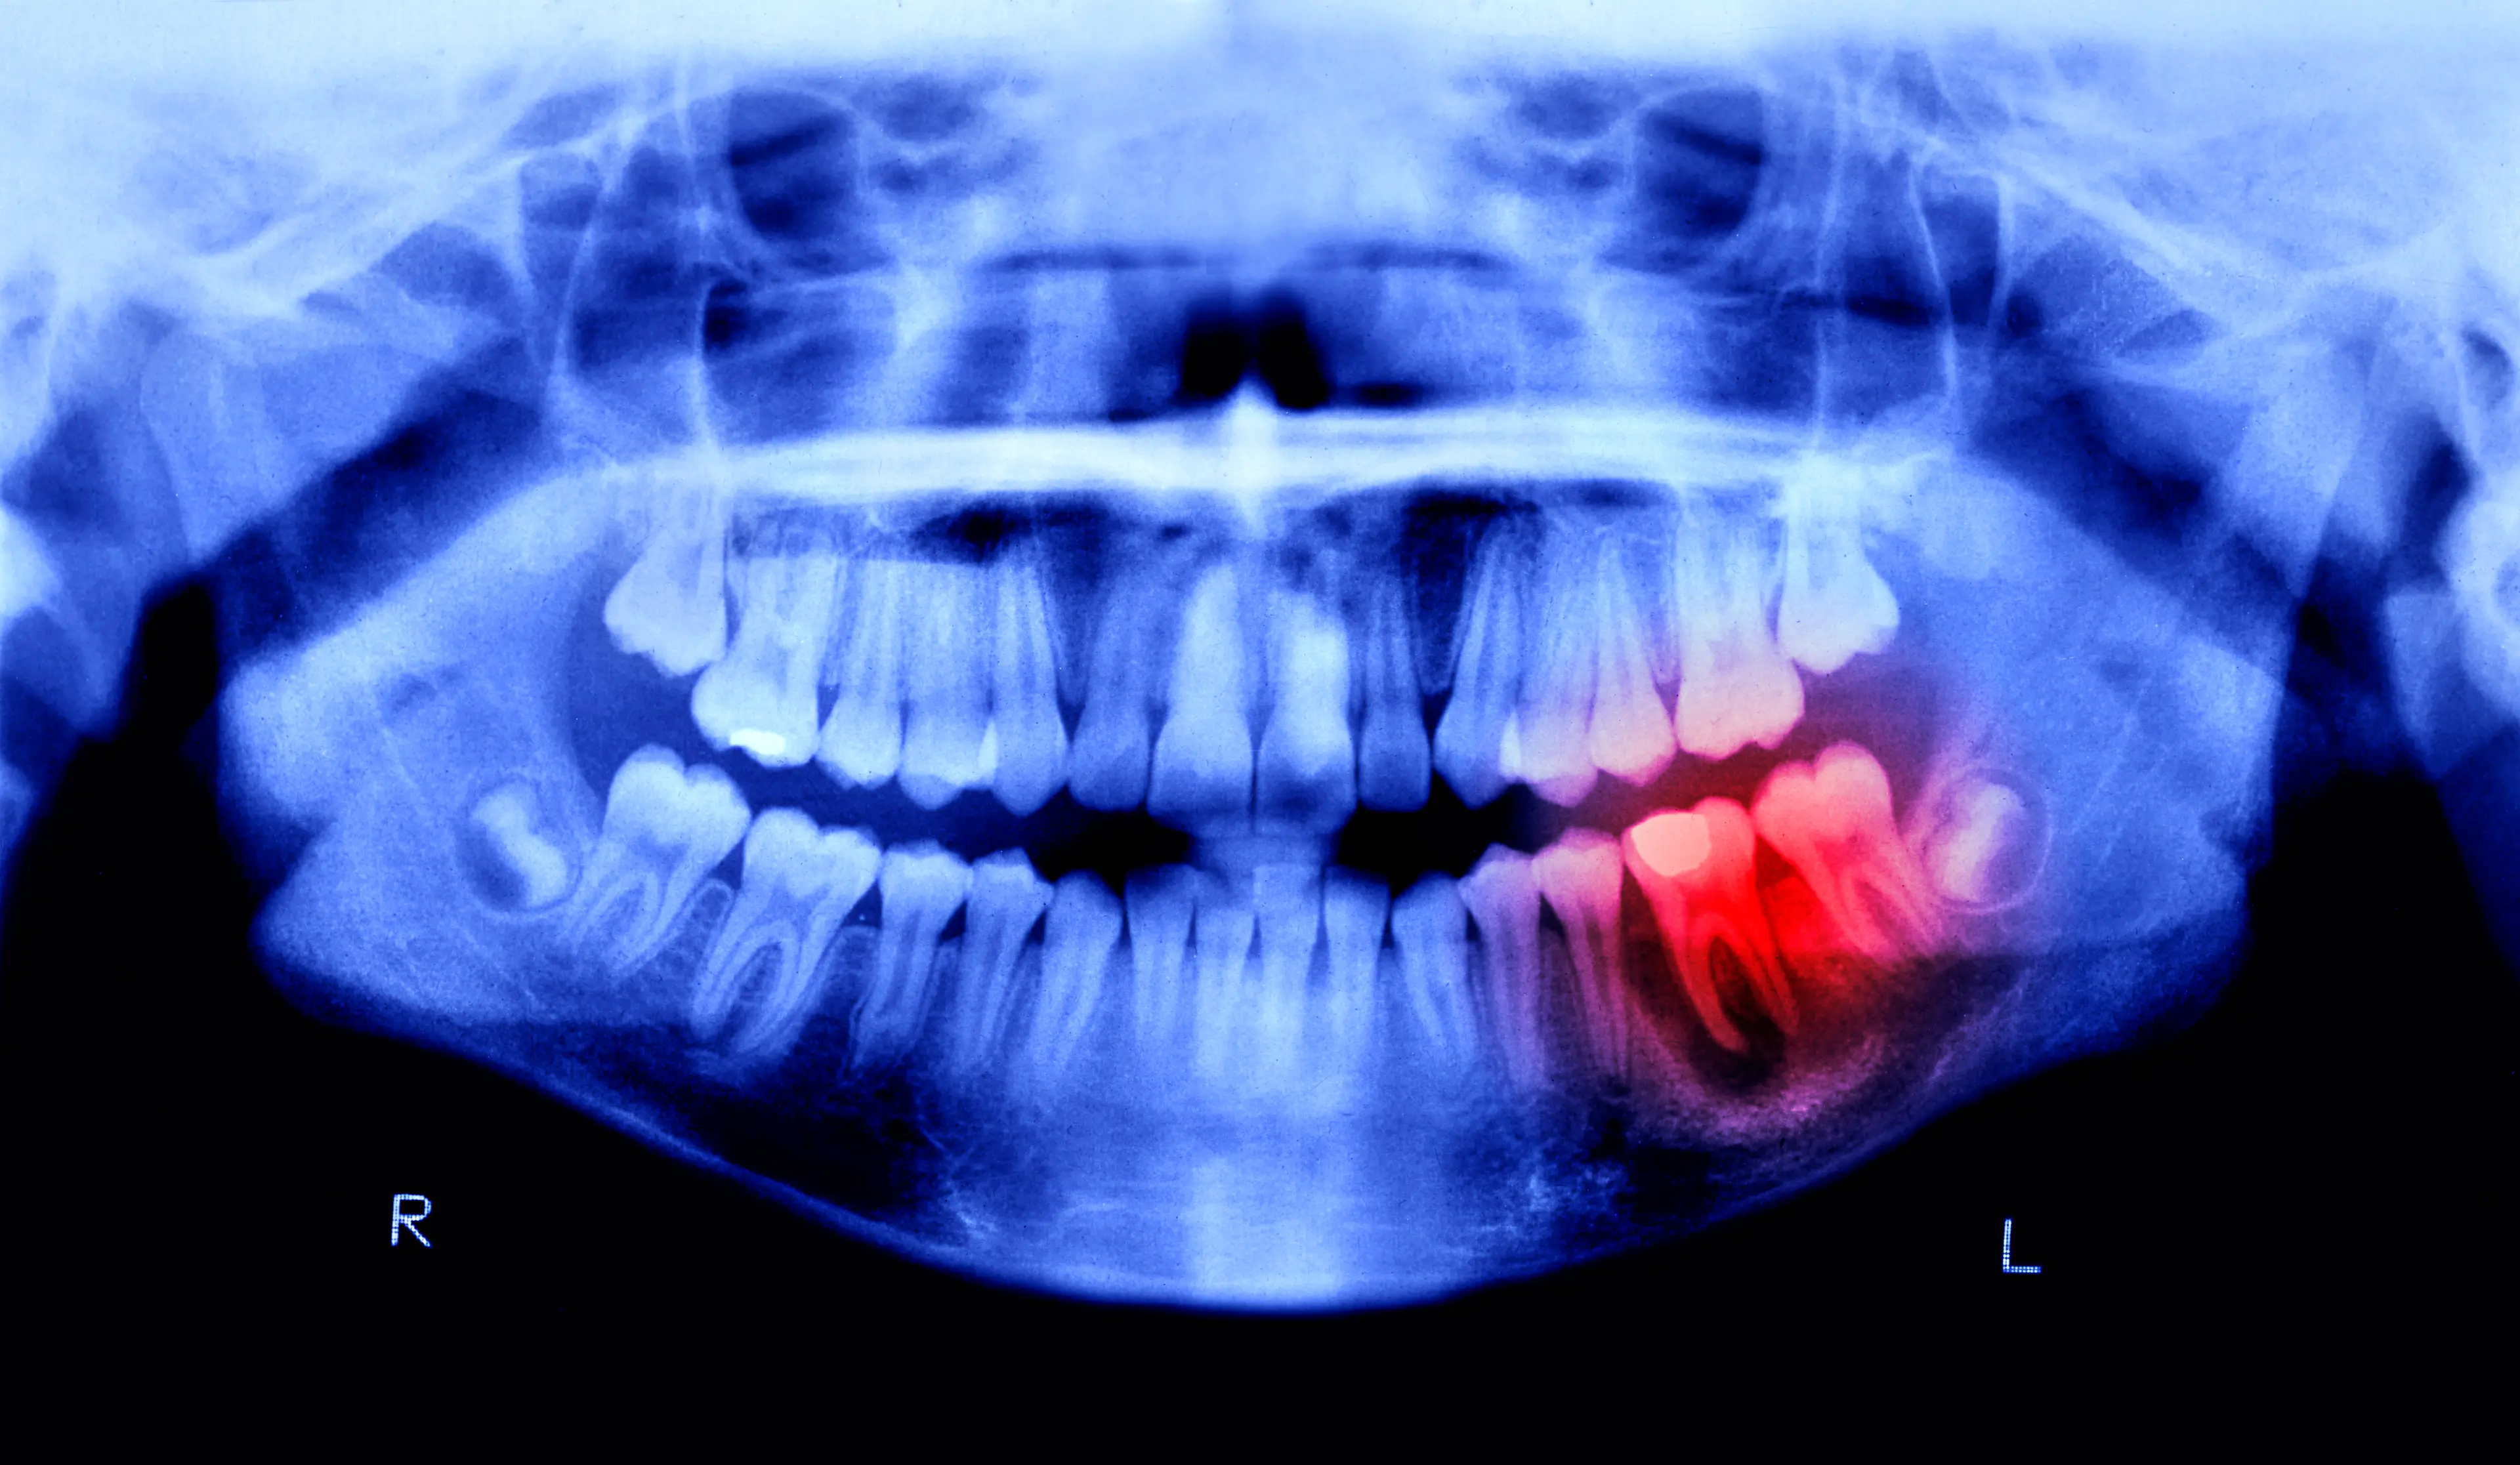

One place where you need to be particularly careful is your mouth, and a dentist has been warning that people regularly neglect this part of the body.

Dr. Chanpreet Kalsi of the Hermes London Dental Clinic said there were warning signs that would be best not ignored, lest you end up with irreversible gum disease.

The first stage of gum disease, known as gingivitis, can be reversed but once it goes beyond that the infection can never be completely removed and you'll be suffering from it forever.

The doc warned that basically half of all adults have non-reversible gum disease, and only 17 percent have perfectly healthy gums.